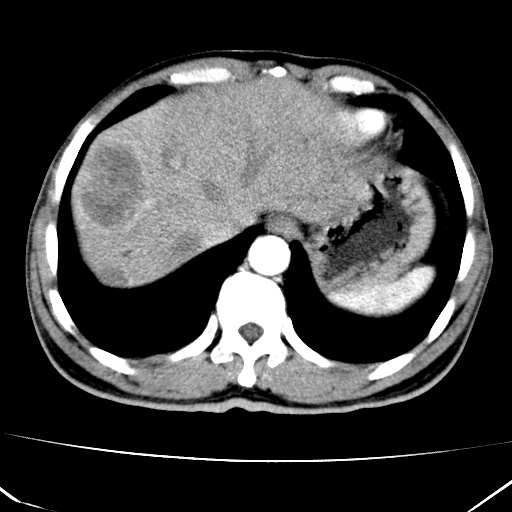

肝脏多发类圆形低密度影,考虑肝脏转移瘤,肝胃韧带一淋巴结肿大,原发?胃癌?

考虑胃癌并肝脏及腹膜后淋巴结转移;不排除淋巴瘤。

肝内转移瘤,腹腔及腹膜后淋巴结转移。